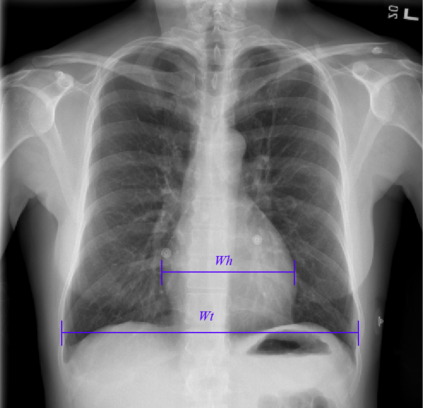

We propose an automated method based on deep learning to compute the cardiothoracic ratio and detect the presence of cardiomegaly from chest radiographs. We develop two separate models to demarcate the heart and chest regions in an X-ray image using bounding boxes and use their outputs to calculate the cardiothoracic ratio. We obtain a sensitivity of 0.96 at a specificity of 0.81 with a mean absolute error of 0.0209 on a held-out test dataset and a sensitivity of 0.84 at a specificity of 0.97 with a mean absolute error of 0.018 on an independent dataset from a different hospital. We also compare three different segmentation model architectures for the proposed method and observe that Attention U-Net yields better results than SE-Resnext U-Net and EfficientNet U-Net. By providing a numeric measurement of the cardiothoracic ratio, we hope to mitigate human subjectivity arising out of visual assessment in the detection of cardiomegaly.